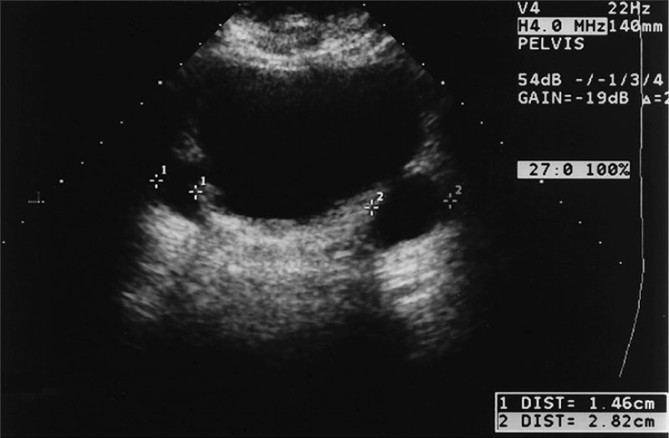

Determine the two different forms of nephrocalcinosis.

What is medullary nephrocalcinosis (left) and cortical nephrocalcinosis (right)?